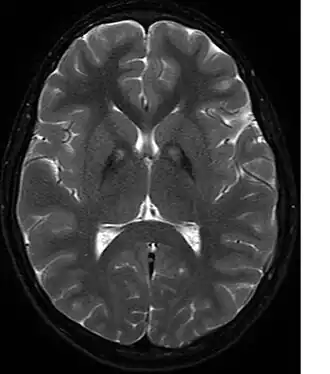

| Sinal do olho do tigre, característico do acumulo de ferro nos núcleos basais. | |

Neurodegeneração associada a pantotenato quinase (PKAN), originalmente conhecida como Síndrome de Hallervorden-Spatz (HSS) é uma síndrome neurodegenerativa caracterizada por um acumulo anormal de pigmentos férricos no globo pálido e na substância nigra.[1] É bastante rara, afetando apenas 1 a 3 crianças em cada milhão de habitantes.